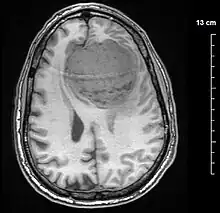

Meningiomas are visualized readily with contrast CT, MRI with gadolinium,[22] and arteriography, all attributed to the fact that meningiomas are extra-axial and vascularized. CSF protein levels are usually found to be elevated when lumbar puncture is used to obtain spinal fluid. On T1-weighted contrast-enhanced MRI, they may show a typical dural tail sign absent in some rare forms of meningiomas.[17]